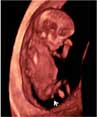

Así se ve un feto de 12 semanas de embarazo en una ecografía en 2D y en un ultrasonidos en 3D. En ambas se distingue los brazos y las piernas.

Podemos ver el bebé de 12 semanas de gestación en una imagen de dos dimensiones (a la izquierda, tumbado) y en tres dimensiones (a la derecha y en posición vertical). Las extremidades del feto (brazos y piernas) son visibles en ambos exámenes ecográficos.